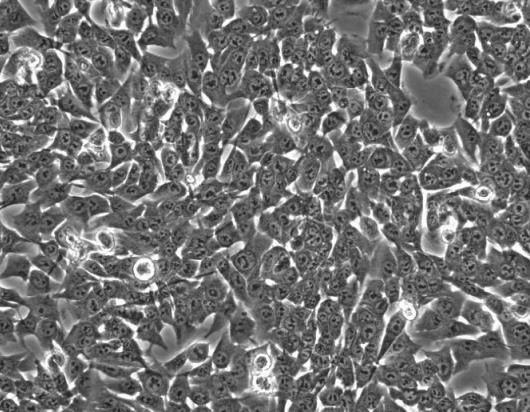

人食道鱗狀癌細(xì)胞(KYSE410)和 TR146 食管鱗狀癌細(xì)胞在多個(gè)方面存在異同點(diǎn)。以下是對兩者異同的詳細(xì)分析:

• 來源:KYSE410 細(xì)胞系來源于人食管鱗狀細(xì)胞癌組織。它在眾多研究中被廣泛應(yīng)用,以探討食管鱗狀細(xì)胞癌的發(fā)生發(fā)展機(jī)制、治療方法等。

• 特性:KYSE410 細(xì)胞具有一定的增殖能力和侵襲性。研究表明,長鏈非編碼 RNA SBF2-AS1 在食管鱗癌組織和 KYSE410 細(xì)胞中高表達(dá),下調(diào) SBF2-AS1 表達(dá)可抑制食管鱗癌細(xì)胞增殖,提高敏感性,其機(jī)制可能與調(diào)控 E2F1 蛋白表達(dá)有關(guān)。此外,蘋果酸舒尼替尼能有效抑制 KYSE410 細(xì)胞的增殖,并誘導(dǎo)其凋亡,機(jī)制可能與哺乳動物雷帕霉素靶蛋白(mTOR)下游通路中 4EBP1 和 S6K1 表達(dá)下調(diào)有關(guān)。

• TR146 細(xì)胞

• 來源:TR146 細(xì)胞同樣來源于人食管鱗狀細(xì)胞癌組織。

• 特性:目前關(guān)于 TR146 細(xì)胞的特性研究相對較少,但一般認(rèn)為其也具有食管鱗狀癌細(xì)胞的典型特征,如增殖、侵襲等能力。